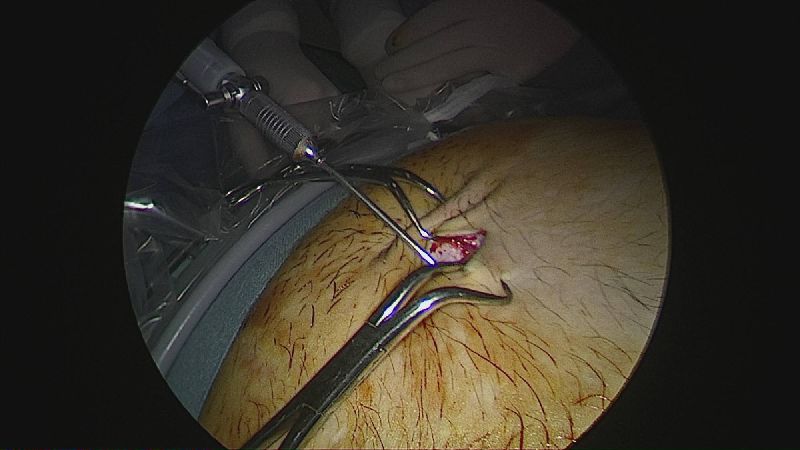

Operația ”de micșorare a stomacului” se realizează miniminvaziv (laparoscopic) și constă în îndepărtarea marii curburi gastrice cu păstrarea antrului gastric și a micii curburi sub forma unui tub calibrat pe o sondă.